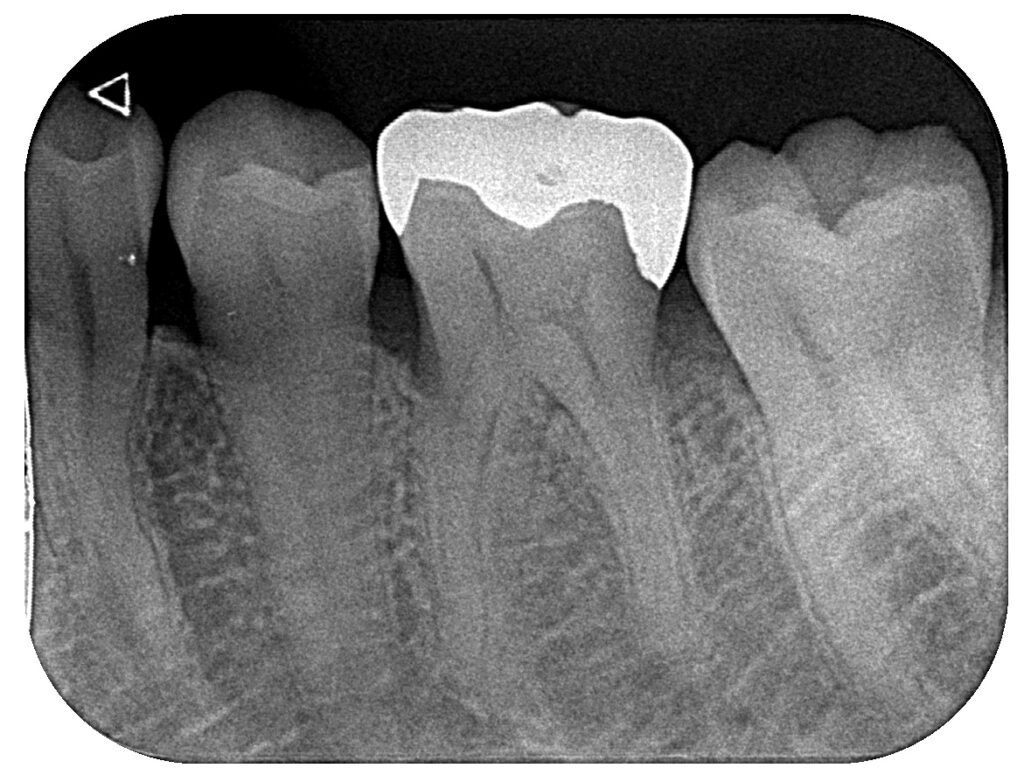

レントゲンおよび口腔内の確認により、

神経まで達した重度の虫歯(C3)を認めました。

その後ラバーダム防湿を行い、インレーと呼ばれる金属を除去。

虫歯を取り除いていくと、根の深い部分からの出血が止まらず

神経を取る処置(抜髄)となりました。

その際に歯に細かなヒビ(クラック)が確認されました。